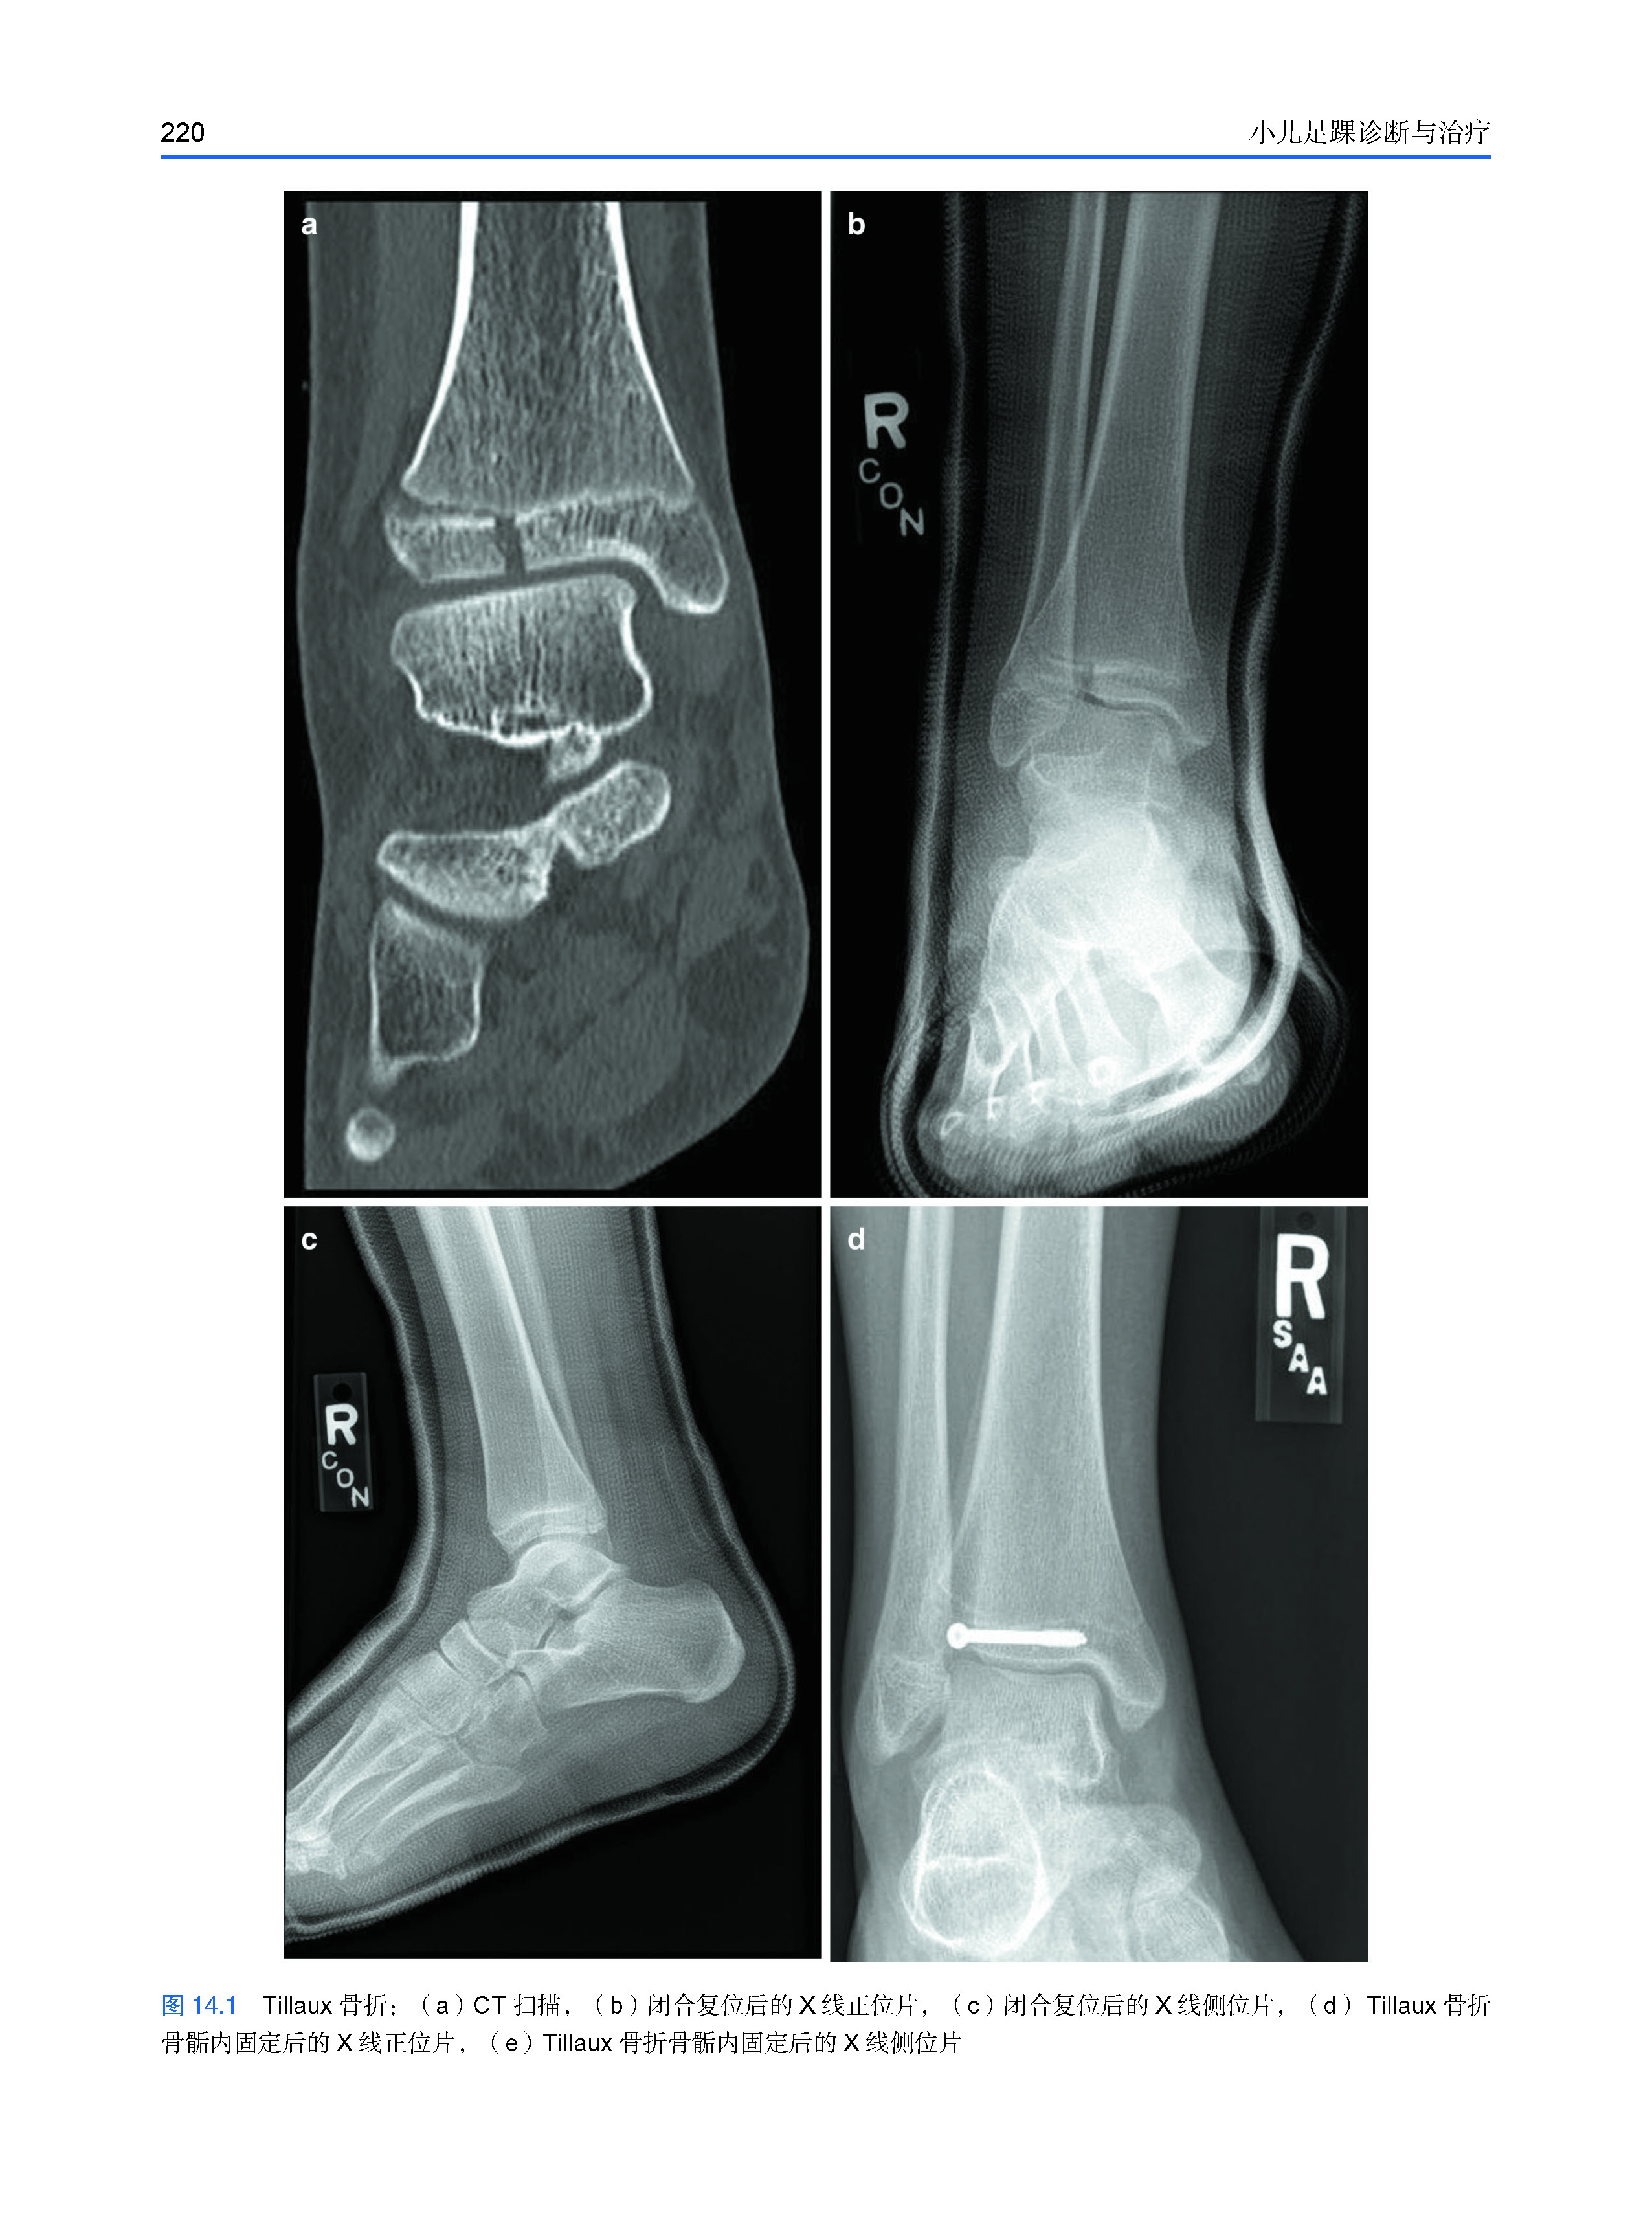

14 儿童足踝骨折